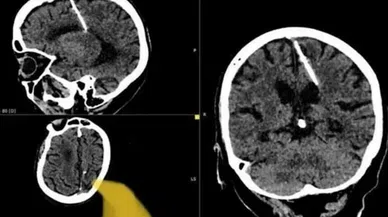

Beyin Haberleri

Son Dakika Beyin Haberleri

Bu sayfada güncel gelişmeleri takip edenler için Beyin ile ilgili en son gelişmeler ve son dakika Beyin haberleri sunulmaktadır. Beyin videoları, Beyin fotoğrafları ve Beyin haberleri